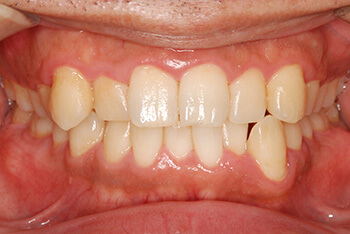

左:初診時。プラークが溜まりやすい不良な被せ物のせいで、歯肉が炎症を起こし赤く腫れています。

右:歯周治療が終了し被せ物を新しく作り直した後。赤く腫れていた歯肉は引き締まり、健康なピンク色に戻りました。